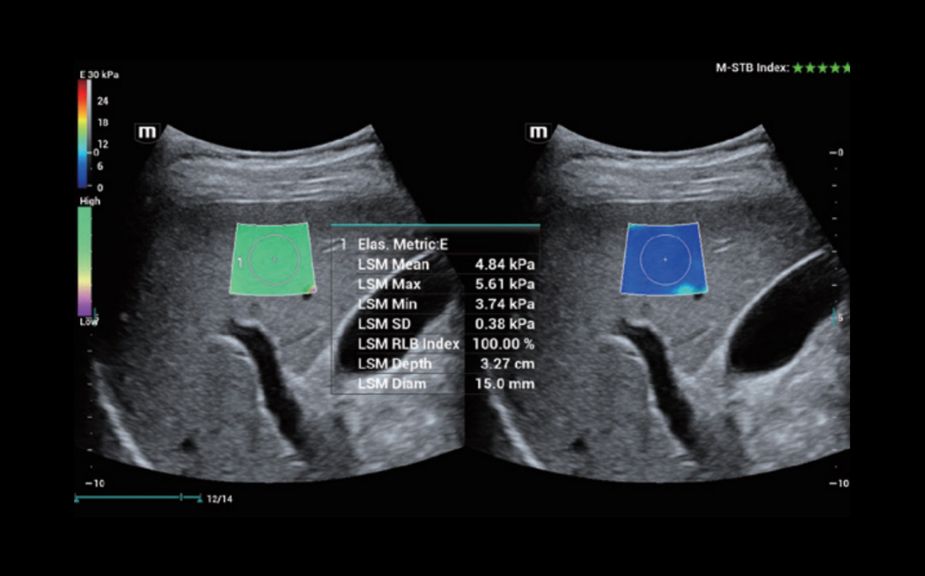

Innovative Stiffness Assessment: HiFR STE

Up to 10 times faster frame rate with smooth STE imaging display

More sensitive motion detection for better stability and greater accuracy

HiFR STE of liver

Innovative Stiffness Assessment: HiFR STE

Up to 10 times faster frame rate with smooth STE imaging display

More sensitive motion detection for better stability and greater accuracy

HiFR STE of liver